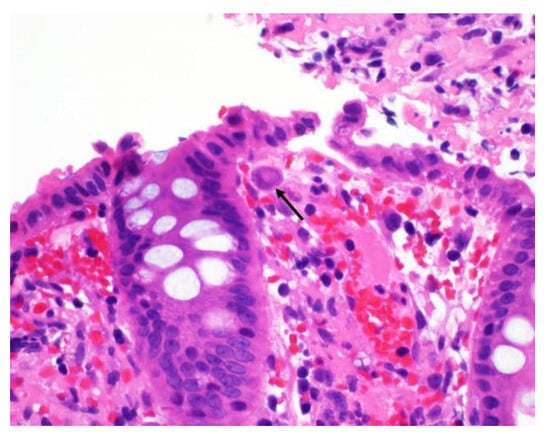

| Histology | Owl’s eye inclusions | Pathognomonic, gold standard |

| Immunohistochemistry (IHC) | CMV antigens in tissues | Sensitive and specific, gold standard |